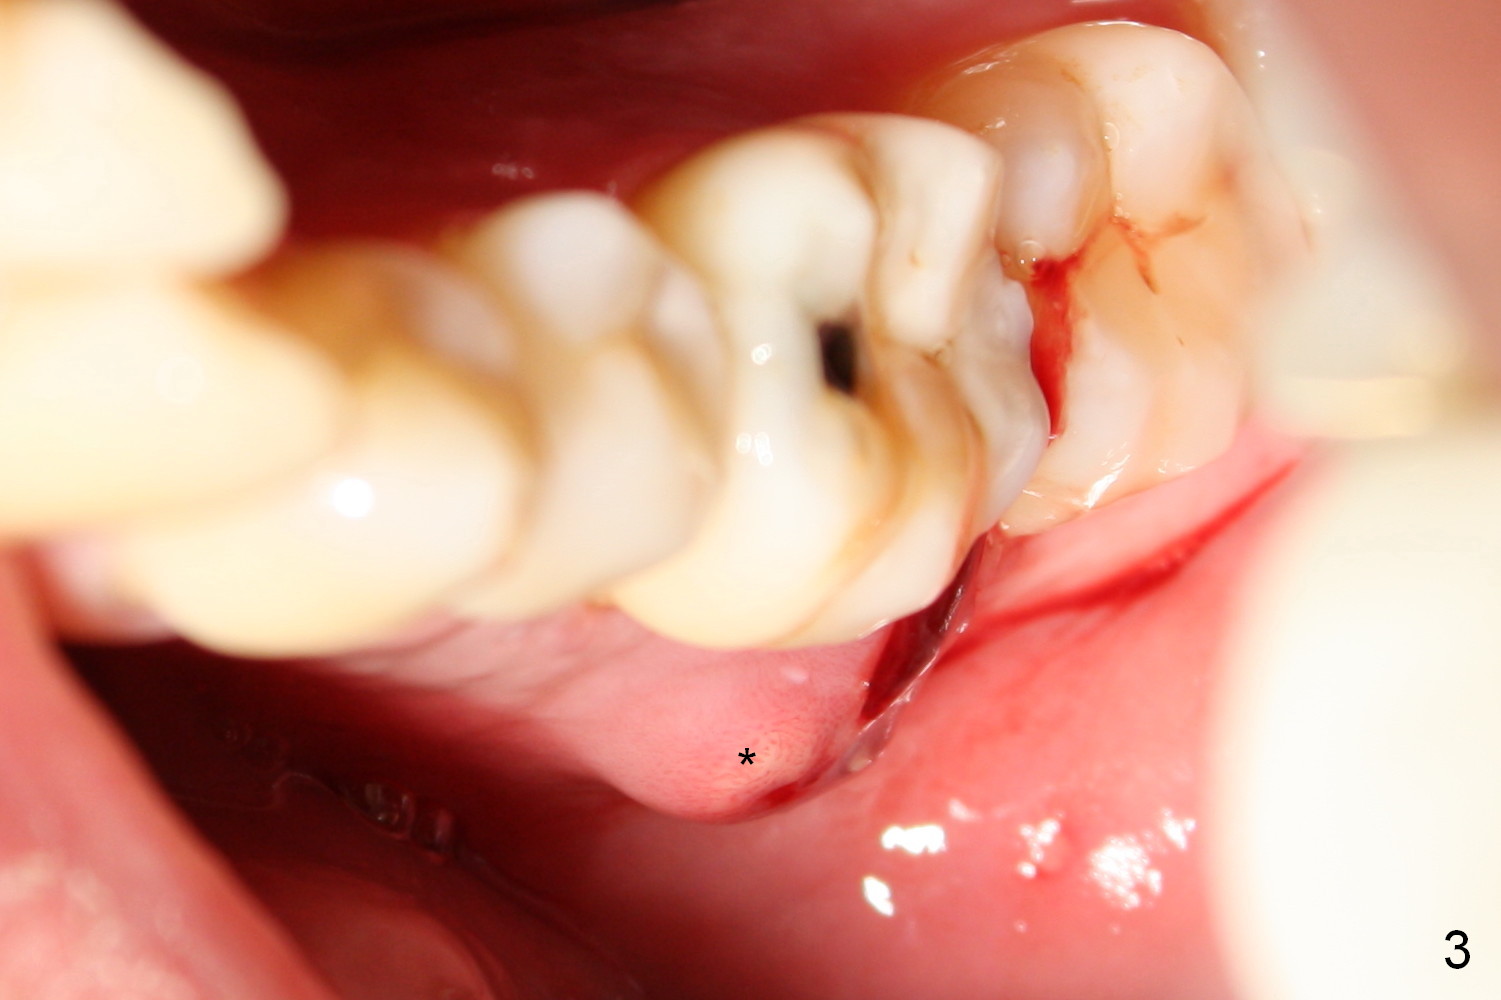

The mesial and distal crests of the tooth #19 were even for a 50-year-old man 7 years ago. Three years later, swelling developed around the distal root with bone loss (Fig.2 *). Three months later, localized swelling occurred (Fig.3 *) with oozing. The patient had thrombopenia (platelet 40 K). The tooth was extracted with suture. There is distolingual root tip resorption. Two months and a half later (Fig.4), a 6x17 mm implant was placed (Fig.5). The implant osteointegrated 5 months postop (Fig.6). The distal crest re-appears 5 months (Fig.7), 2 years (Fig.8) and 2 years 8 months (Fig.10) post cementation. At the last appointment, the patient complained of pain and swelling at #30 with mesial bone loss (Fig.10 *), as compared to Fig.9 taken 9 years ago. The mesiolingual pocket is deep. After scaling and Chlorhexidine irrigation, Arestin is locally administered.